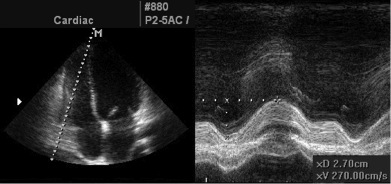

Товщина стінки ПШ. Товщина стінки ПШ вимірюється в діастолу, бажано з субкостальної позиції в М- чи В-режимі (Рис. 5). В якості альтернативи для вимірювання товщини стінки ПШ можна також використовувати парастернальні доступи. Товщина >5 мм вказує на гіпертрофію ПШ (ГПШ) та може говорити про перенавантаження ПШ тиском при відсутності іншої патології.

Товщина стінки ПШ. Товщина стінки ПШ є корисним виміром для виявлення ГПШ, що звичайно розвивається в умовах його перенавантаження тиском (підвищення СТПШ) [19-21]. Збільшення товщини стінки ПШ можна побачити при інфільтративних чи гіпертрофічних кардіоміопатіях, а також у пацієнтів з вираженою гіпертрофією ЛШ навіть за відсутності ЛГ [19]. Товщину свобідної стінки ПШ можна виміряти в М- чи В-режимі з субкостальної позиції, бажано на рівні кінчика передньої стулки трикуспідального клапана, або з лівих парастернальних зрізів [6, 18]. З субкостальної позиції легко вирівняти напрямок ультразвукового променя перпендикулярно свободній стінці ПШ. Критичним для акуратного виміру є виключення трабекулярності та папілярних м’язів ПП з ендокардіальної поверхні ПШ. Зсув фокусу на область стінки ПШ та зменшення глибини сканування звичайно допомагає поліпшити розрішення ендокардіальної границі. Також треба ретельно слідкувати за тим, щоб виключити з виміру епікардіальний жир.

Рекомендації: Аномальне потовщення стінки ПШ має бути описане в протоколі при наявності, у пацієнта з підозрою на дисфункцію ПШ та / або ЛШ, використовуючи верхню межу норми 0,5 см з PLAX або субкостального доступу (Таб. 2).

Рис. 5. Вимірювання товщини стінки ПШ. А. Субкостальне зображення у 2D стінки ПШ. В. Збільшене зображеня в режимі «zoom» регіону виділеного на зображенні А з товщиною стінки, означеною стрілками. С. Зображення в М-режимі, що відповідає стрілка на зображенні В. D. Режим «zoom» позначеного на зображенні С регіону – товщина стінки ПШ наприкінці діастоли [3].